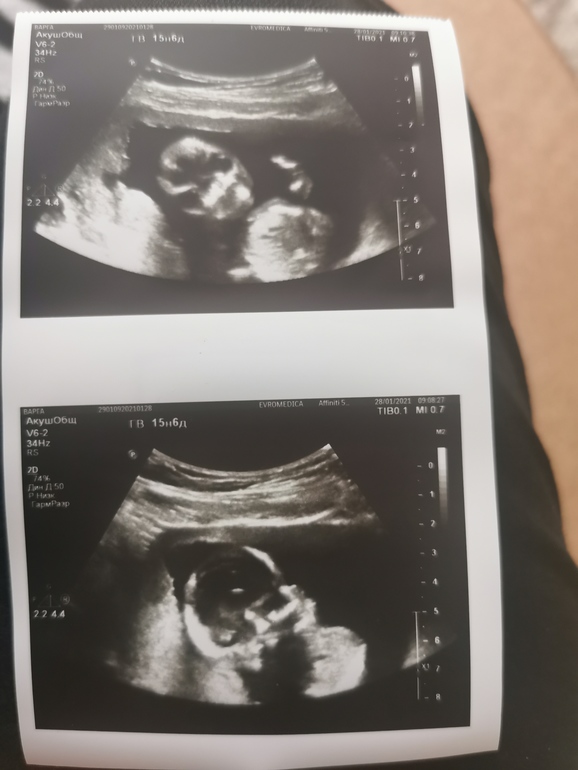

Мы узнали, кто в домике живёт ❤️

Пол малышаПо месячным срок 15.6. С нашей крохой все хорошо, и эта девочка. Плацента уже не перекрывает зев, низко доходит до внутреннего зева.

БПР 35 мм

ОГ 130мм

ОЖ 94 мм

ДБ 20/20 мм

Плечевая кость 20/20 мм. Предполагаемый вес 135 гр. Наша малышка. Как мы счастливы,) Честно не представляю, как девочку воспитывать, сыну 10 лет.